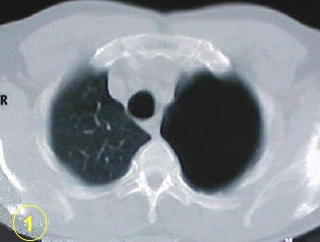

La tomografía computarizada del tórax

y su adecuada interpretación es de gran ayuda diagnóstica

en las patologias del tórax.